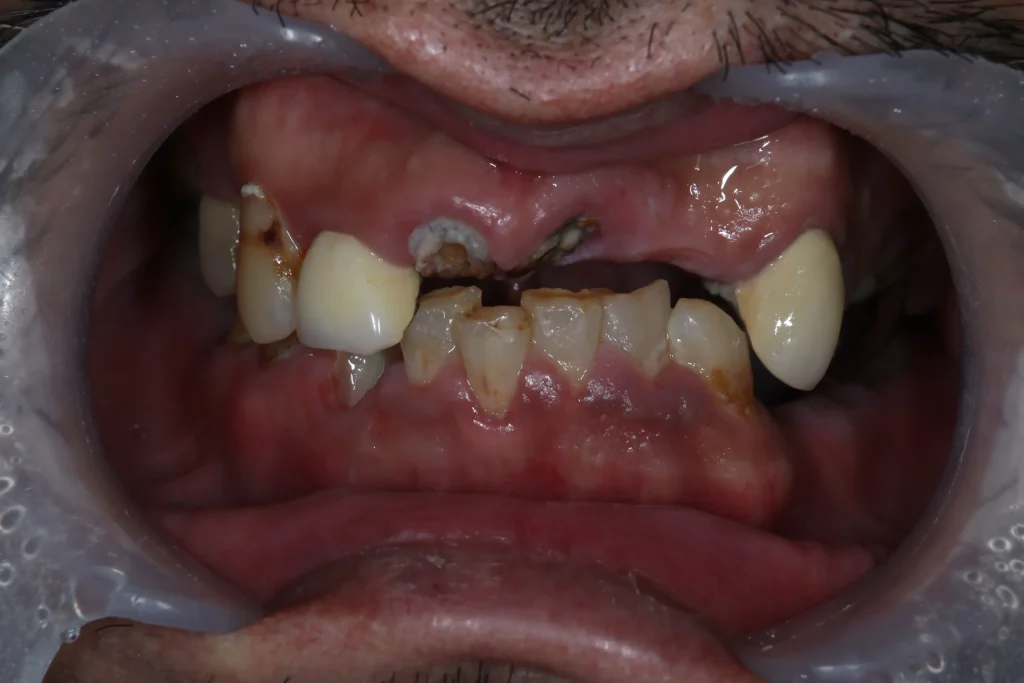

噛み合わせが崩れる

歯は1本だけで機能しているわけではありません。

全体のバランスで噛み合わせが作られています。

そのため歯が抜けたまま放置すると

- 噛むバランスが崩れる

- 反対側ばかりで噛む

- 他の歯に負担がかかる

といった状態になります。

結果として

残っている他の歯が破折したり、被せ物が取れたり、揺れてきたりして

残っている歯の寿命が短くなる可能性があります。